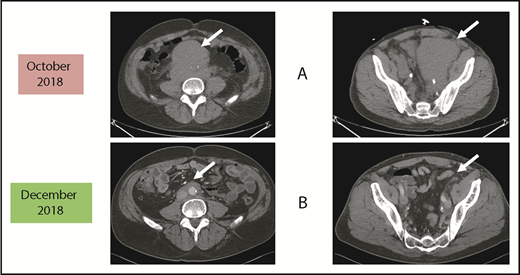

Before and after 3 months of acalabrutinib. A 54-year-old man was diagnosed with stage IVB MCL in 2014. He received chemoimmunotherapy including cytosine arabinoside and an adjuvant autologous SCT. (A) In 2018, he relapsed with left leg swelling due to bulky pelvic disease and a new deep vein thrombosis. (B) After biopsy proof of relapsed MCL, he received acalabrutinib 100 mg twice daily, rituximab, and apixaban; within 3 months, he achieved a marked response with no side effects of the combination. He has returned to full-time work and continues on therapy as of January 2019.

Patients who relapse are typically treated with salvage chemoimmunotherapy or other approved agents. These include the proteasome inhibitor bortezomib,13,14 the immunomodulatory agent lenalidomide,15-19 the mammalian target of rapamycin complex 1 inhibitor temsirolimus (Europe, not United States),20-24 and the Bruton tyrosine kinase (BTK) inhibitors discussed in the next section.25-29 The bcl-2 inhibitor venetoclax has orphan drug designation (but not approval) for MCL.30,31 Despite the plethora of agents for this disease, most patients will need all of them during their lifetime. Thus, there is always a need for additional agents as illustrated by the case described in Figure 1.